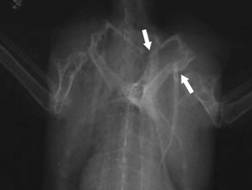

Elbow luxation in

the mediolateral radiation duct: completely torn off

ligament |

the caudocranial radiation duct |